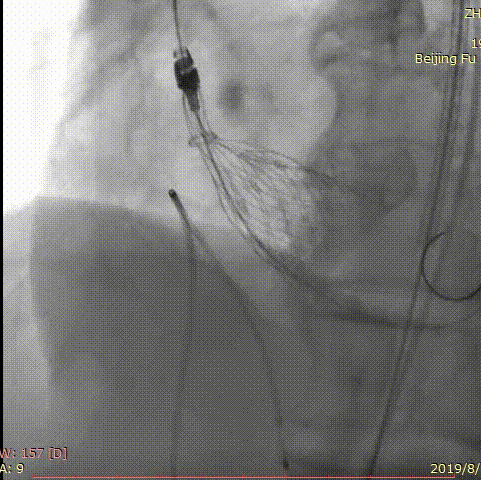

第一例手术的患者是一位86岁男性,间断胸闷症状2月,入院后超声提示主动脉瓣重度狭窄并少中量反流,平均跨瓣压差60mmHg,收缩期峰值流速4.9m/s,最大压差96mmHg。术前CT评估主动脉瓣环22.6*28.5mm,周长80.2mm,面积498.8mm2,右侧股动脉为主入路,应用24mm微创心通敖广球囊预扩张,植入27mm微创心通Vifaflow瓣膜,术后造影提示无瓣周漏,超声提示主动脉瓣跨瓣无压差。

术前影像